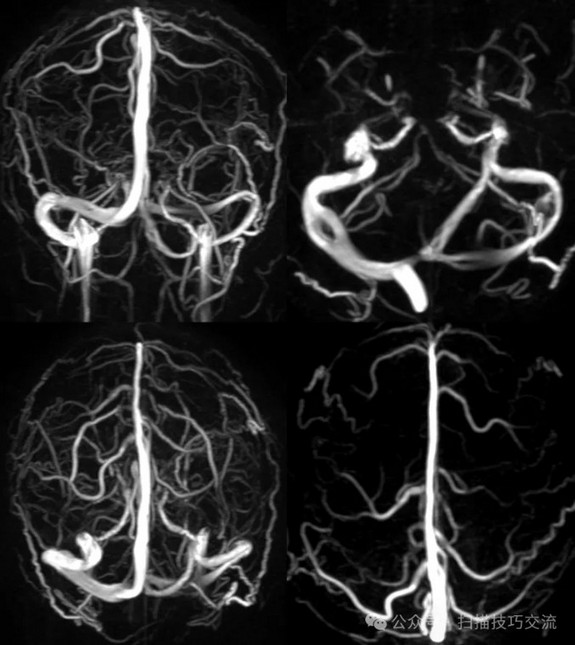

临床申请:颅脑平扫,静脉成像,磁敏感成像,颅内静脉血管黑血成像。

PC-MRV未见异常。